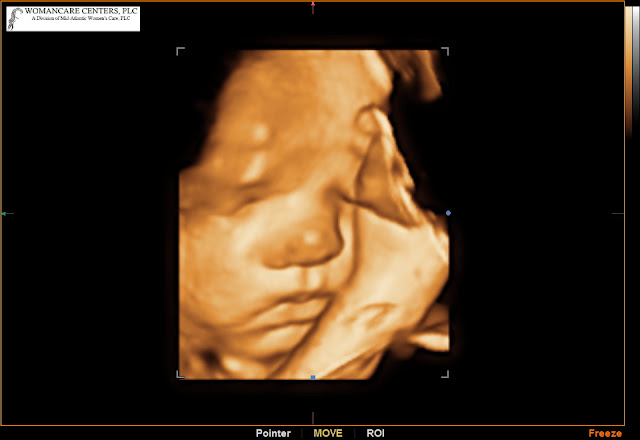

Portia Liberty : 34 Weeks

Portia Liberty Nowak had her toes against her forehead last we saw her. Quite the little pretzel. She looks a good deal like her sister across her nose and pouty lips, and I look forward to observing all of their similarities and differences.